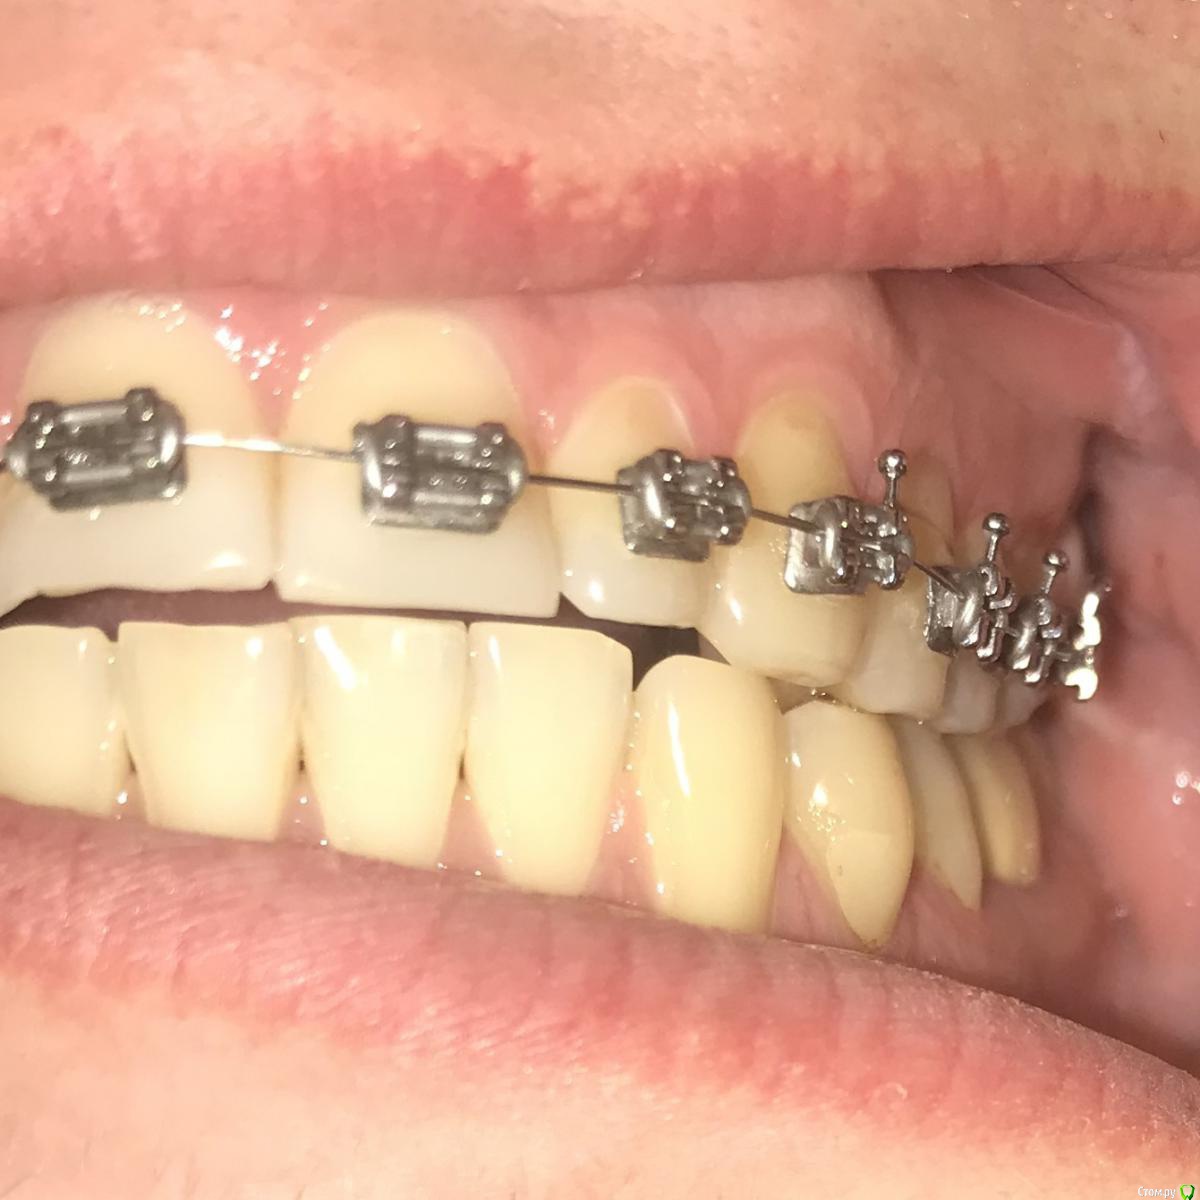

Ситуация такая, что начал лечение у ортодонта, но как оказалось, сильно исправлять прикус он не будет, только выравнивание зубного ряда. Расстояние выноса верхних зубов вперед в ширину четверки, но удалять четверки мне бы не хотелось. Так же, есть смещение в бок. Есть одна коронка и одна вкладка, много зубных каналов запломбировано. В целом, сильных проблем с прикусом я не ощущаю, но не будет ли потом проблем с челюстным суставом? Морально я готов к лечению, хотелось бы все сделать раз и навсегда, но с чего начать, какими способами нужно будет все исправлять? Придется ли делать операцию на челюсти или как то выносить нижнюю челюсть вперед другими способами? Нужно ли удалять восьмерки(осталась пара)?

И самое главное, необходимо найти грамотного специалиста и клинику, очень не хотелось бы иметь какие то проблемы со здоровьем после всех изменений, а так же бесконечного перелечивания, как у некоторых. Мне 31. Буду благодарен, если кто посоветует врача, желательно по собственному опыту или по хорошим отзывам в городе Москва, южная часть Подмосковья.